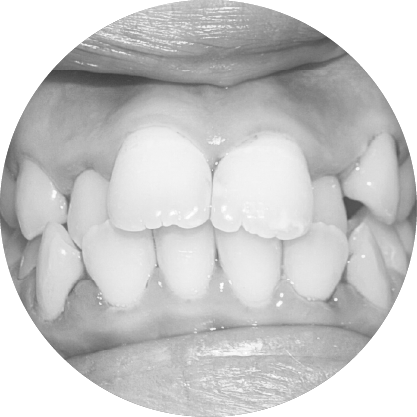

ตัวอย่างในชีวิตจริง

ช่องว่างระหว่างฟัน (Diastema)

การปิดช่องว่างระหว่างฟัน เพื่อรอยยิ้มที่สมบูรณ์แบบ

"ช่องว่างระหว่างฟันหรือไดแอสเทมา หมายถึงช่องว่างระหว่างฟันที่เห็นได้ชัด ซึ่งอาจเป็นปัญหาทางความงามสำหรับหลายๆ คนการจัดฟันสามารถปิดช่องว่าง เหล่านี้ได้อย่างมีประสิทธิภาพทำให้มีรอยยิ้มที่สม่ำเสมอและสวยงาม"